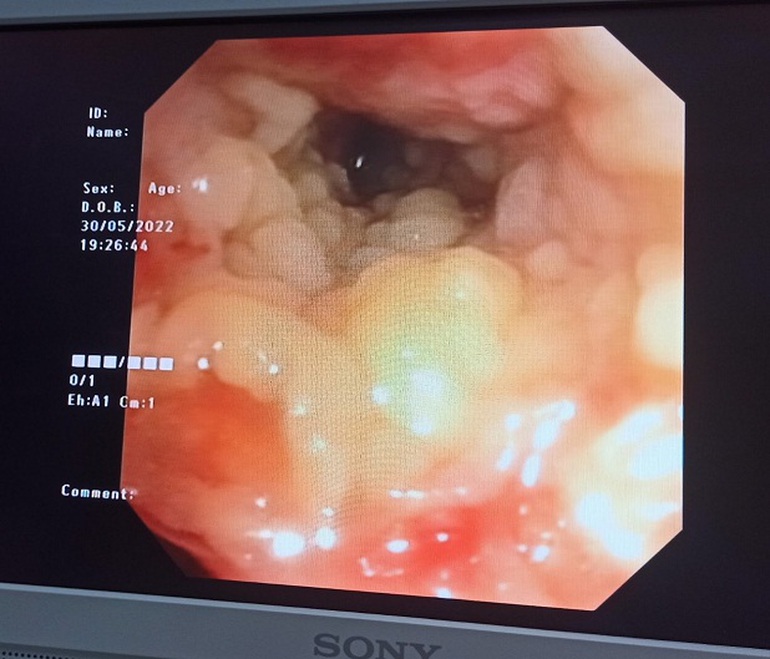

Ngay trong ngày 30/5, bệnh nhân được nội soi phế quản xuất hiện nhiều các mảng giả mạc thùy dưới phổi 2 bên.

BS Cường cho biết, với kinh nghiệm điều trị cho nhiều ca phức tạp, các bác sĩ đã nghĩ ngay đến nấm. Kết quả nội soi phế quản một ngày sau đó cũng cho thấy giả mạc phát triển trên toàn bộ niêm mạc đường thở tạo nên các đám sùi và các giả mạc đan xen nhau như mạng nhện lấp kín hết lòng khí phế quản.

Hình ảnh nội soi phế quản 1/6 cho thấy giả mạc lan rộng toàn bộ niêm mạc đường thở và giả mạc tập trung như mạng nhện lấp kín phế quản.